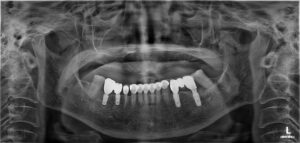

일단 뿌리가 파절된 치아와 염증이 진행 중인

치아 3개를 발치한 후 양쪽으로

각 2개씩 임플란트를 식립하고,

나머지 브릿지로 연결된 치아는 잘라서

그대로 사용하여 시린 치아만 따로 신경치료 후

다시 크라운 수복을 진행하기로 하였습니다.

치료 전, 후 사진을 보시게 되면

염증이 깔끔하게 제거되고 남가좌동임플란트가

안정적으로 식립되어 잇는 모습과

시린 증상이 있던 치아의 뿌리 끝까지

신경치료가 마무리되어 있는 모습을 보실 수 있습니다.